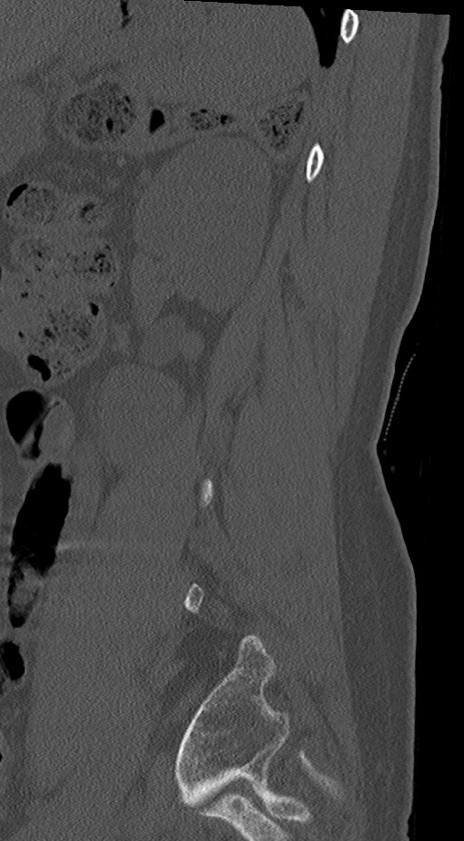

腰椎CT

冠状断像